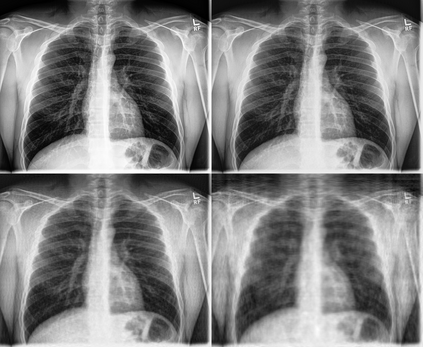

Super-resolution, in-painting, whole-image generation, unpaired style-transfer, and network-constrained image reconstruction each include an aspect of machine-learned image synthesis where the actual ground truth is not known at time of use. It is generally difficult to quantitatively and authoritatively evaluate the quality of synthetic images; however, in mission-critical biomedical scenarios robust evaluation is paramount. In this work, all practical image-to-image comparisons really are relative qualifications, not absolute difference quantifications; and, therefore, meaningful evaluation of generated image quality can be accomplished using the Tversky Index, which is a well-established measure for assessing perceptual similarity. This evaluation procedure is developed and then demonstrated using multiple image data sets, both real and simulated. The main result is that when the subjectivity and intrinsic deficiencies of any feature-encoding choice are put upfront, Tversky's method leads to intuitive results, whereas traditional methods based on summarizing distances in deep feature spaces do not.